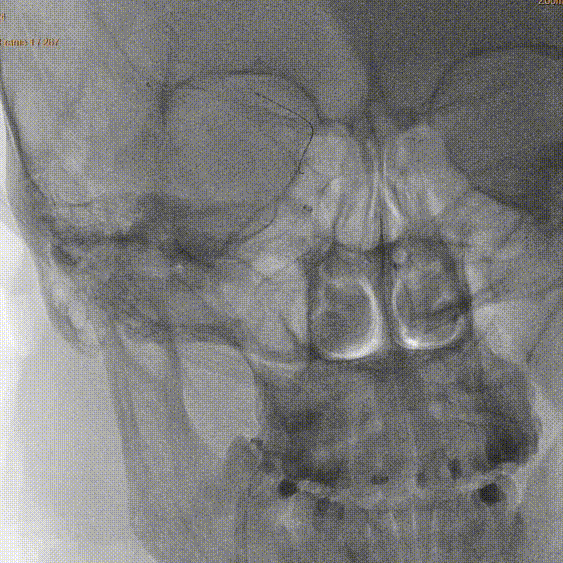

术前MRA:右侧大脑中动脉闭塞。

评估病变及代偿:Ⅰ型弓,右侧大脑中动脉闭塞,软脑膜动脉、大脑前动脉对其部分代偿,ASITN/SIR 2级。

术前DSA造影